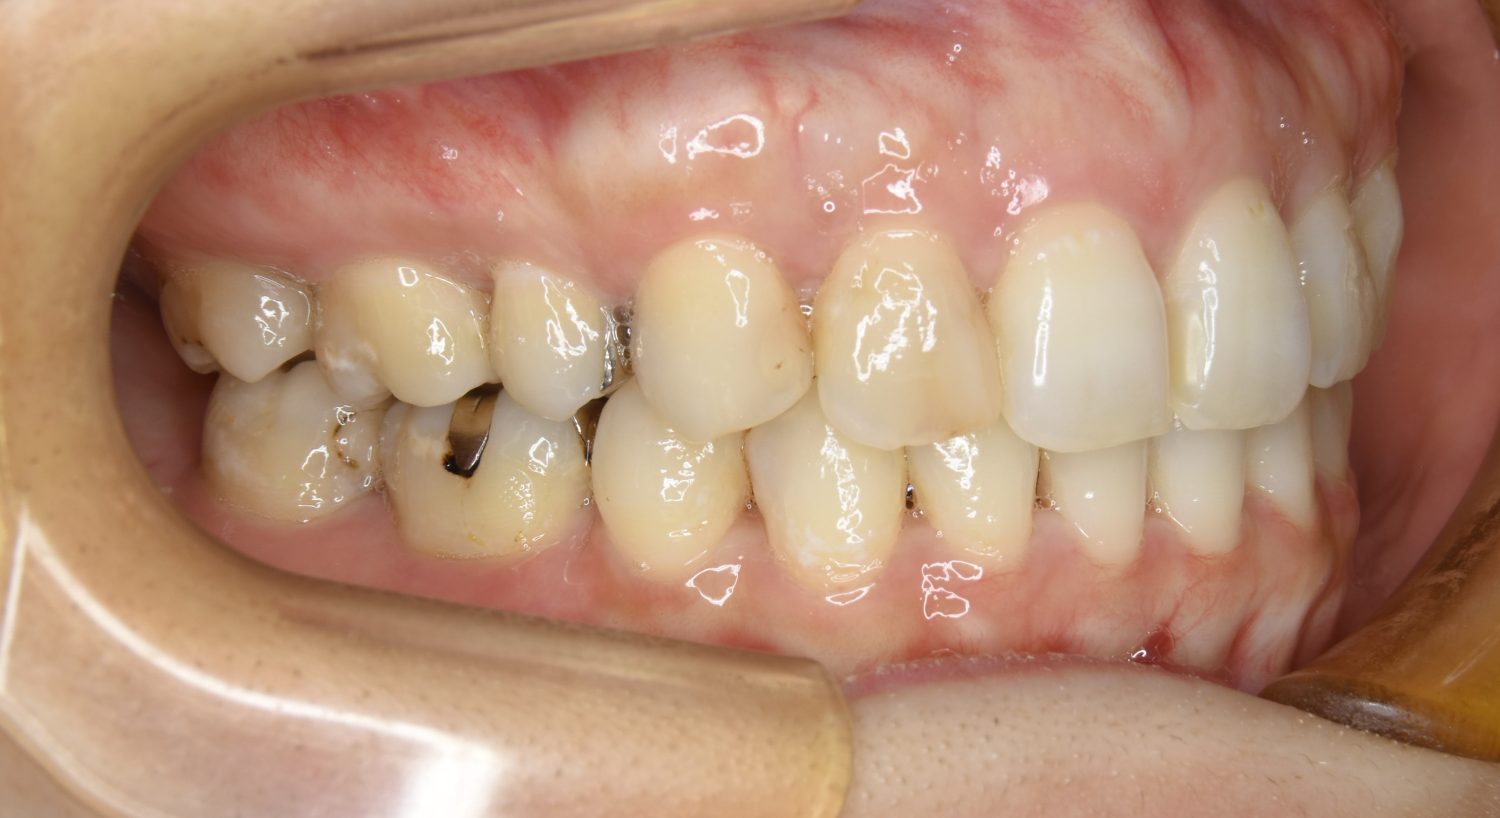

前歯部開咬の症例紹介②

Before

After

主訴

前歯で物が噛めない

治療内容

上下ラビアルブラケット(唇側装置)に矯正用アンカースクリューを併用し非抜歯で治療を行いました。

治療費

1,000,000 円(税込)

治療期間

26ヶ月

通院回数

27回

想定されたリスク

※歯根吸収、歯肉退縮、歯髄壊死、顎関節症状

丸山和宏先生

ピーススマイル矯正歯科

上下の前歯が開いており前歯では全く噛めていない状態でした。臼歯の圧下を行うことで機能面のみでなく審美面も改善しました。